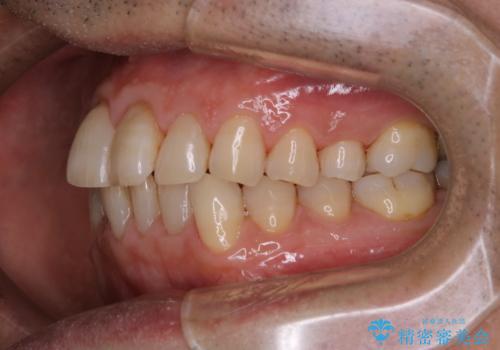

インビザラインでのマウスピース矯正中にPMTCで着色をきれいに

- インビザラインでの矯正治療中の方です。コーヒーをよく飲むため、着色が気になるとのことでした。PMTC60分コースを行いました。

PMTC(保険外治療)は、毎日の歯磨きで落としきれない汚れや、コーヒ、紅茶・タバコのヤニなどの着色も除去します。目には見えない歯と歯の間・歯肉の境目・インビザライン中はアタッチメント周囲などに残っているプラーク(歯垢)もしっかり取り除きます。PMTCでは専門的な機械や材料を使用して、徹底的に汚れを除去するため、虫歯・歯周病・口臭予防などにつながります。

また、仕上げのトリートメントでは歯の表面の凸凹にミネラルを補給して、ツルツルの表面に仕上げます。定期的にPMTCを行うことにより、歯質の強化になり着色がつきにくい状態になります。